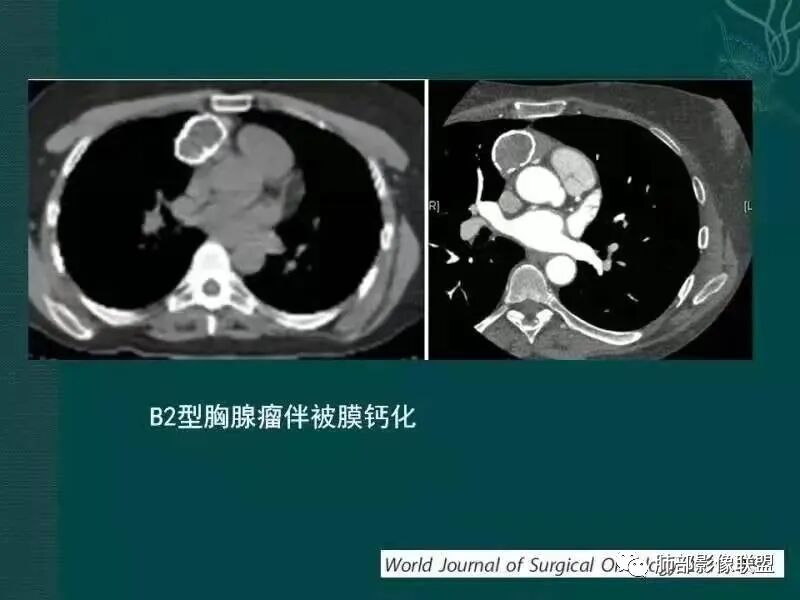

肿块边界清楚,低密度纤维间隔,未见侵犯转移及增大淋巴结,多见于胸腺瘤AB型

—强化程度及强化方式不支持常见的血管瘤及巨淋巴结增生症(CD)。